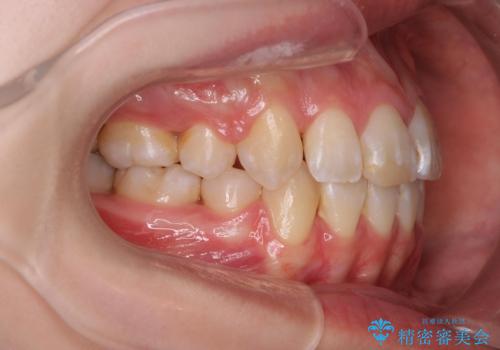

綺麗な歯並びを手に入れられたと同時に、口元もスッキリし、仕上がりに満足いただくことができました。

突き出た前歯を治したい 小臼歯抜歯+マルチブラケット矯正

前歯の角度を改善するために小臼歯4本の抜歯を行いワイヤー マルチブラケットを用いて、しっかりと前歯の角度を改善する治療計画としました。